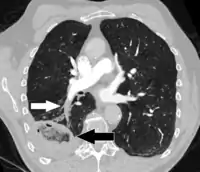

CT scan of a lung infarction because of chronic pulmonary embolism (white arrow). The infarcted area (black arrow) has a reverse halo sign.

CT scan of a lung infarction because of chronic pulmonary embolism (white arrow). The infarcted area (black arrow) has a reverse halo sign.